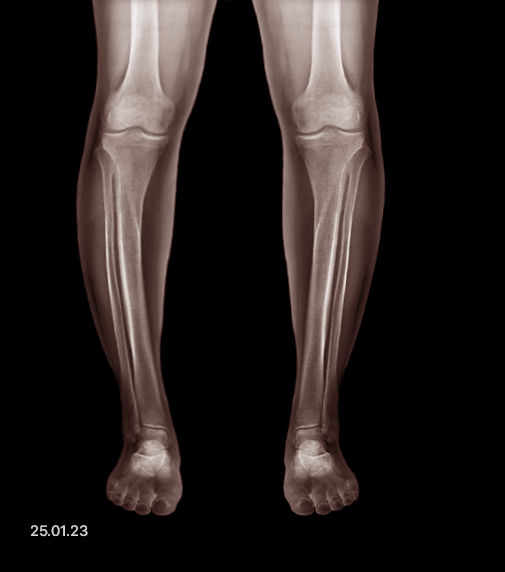

Before and After

- Before

- After